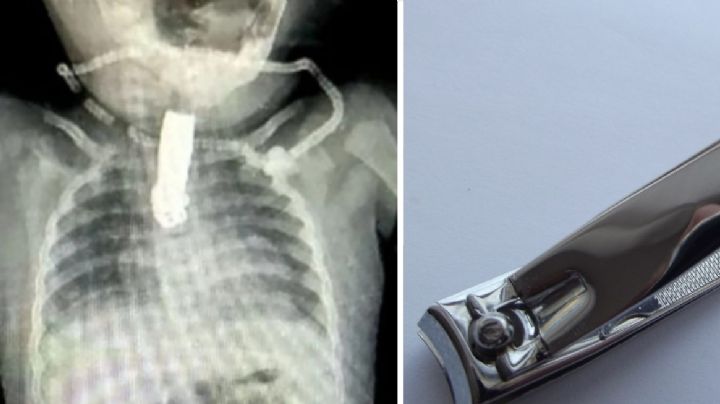

¿Para qué sirve el hoyo del cortauñas?; descubre sus sorprendentes usos

19/2/2025 | Conocer sus múltiples funciones no solo te ayudará a aprovechar al máximo esta herramienta, sino que también te permitirá mantenerla organizada y accesible